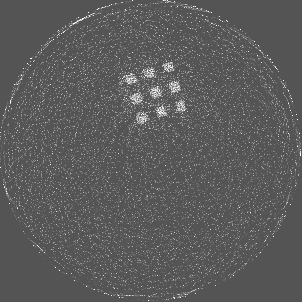

Figure 7 shows a single slice spectral reconstruction of the Mg scaffold. Due to low atomic number of Mg (Z = 12) compared to Ti (Z = 22), the results did not exhibit any significant beam hardening effects. Low energy reconstruction shows good spatial information while high energy ranges are limited by photon noise. In scans involving smaller samples made from low-Z materials like Al or Mg, acquiring low energy quanta in CSM provide high spatial information with minimum or no beam hardening effects. Figure 8 illustrates a single slice spectral reconstruction of the Ti mesh. Similar to the Ti scaffold, streaks are less pronounced in the mid and high energy ranges.